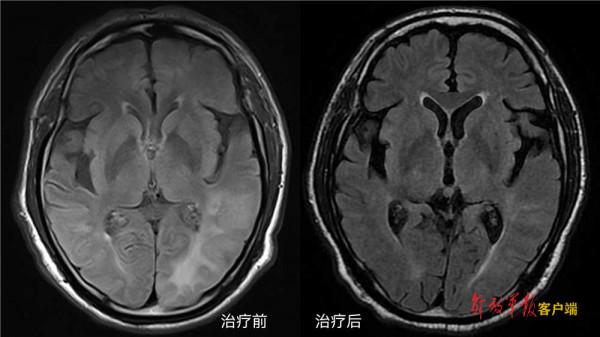

治療一週後,患者視物變清晰,顱內病灶明顯消退。治療第二週,患者腦內病灶基本消失,視力基本恢復,認知障礙也得到改善,蒙特利爾認知評分由入院的18分迅速提升到23分,胸水及心包積液消失。